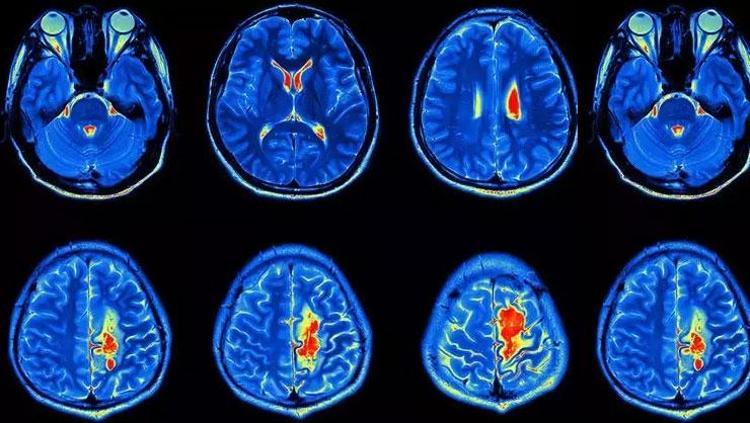

Epilepsiye neden olan gizli beyin bozukluklarını ortaya çıkaran yapay zekâ, teşhis sürecinde devrim yarattı. MR ve PET görüntülerini analiz eden sistem, yüzde 90’ın üzerinde başarı oranına ulaştı. Uzmanlara göre bu buluş, tedaviye yanıt vermeyen birçok çocuk için yeni bir umut olabilir.

Araştırma, kortikal displazi ve fokal epilepsi tanısı bulunan çocuklar üzerinde gerçekleştirildi. Önceden MR sonuçları “normal” olarak değerlendirilen bu hastaların yüzde 80’inde aslında gizli lezyonlar olduğu ortaya çıktı.

Yapay zekâ modeli hem MR hem de PET görüntülerini analiz ettiğinde, bir test grubunda yüzde 94, diğerinde yüzde 91 oranında doğruluk elde etti. İlk grupta yer alan 17 çocuktan 12’si beyin lezyonlarının alınması için ameliyat edildi ve bunlardan 11’i artık nöbet yaşamıyor.